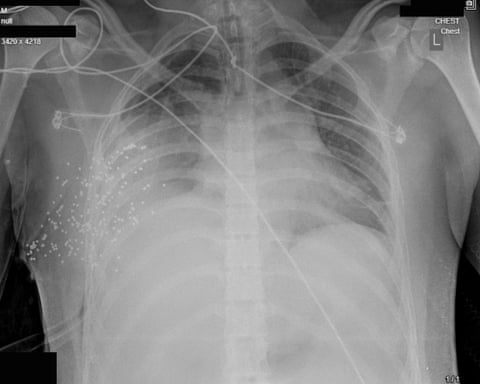

Більшість поранень спричинені дробовими патронами та кулями високого калібру з автоматичної зброї, які застосовували Іранські Революційні гвардії. При близькому обстрілі дробові патрони діють як сотні маленьких куль одночасно, руйнуючи м’які тканини обличчя, грудної клітки та очей. Наприклад, у випадку юнака на ім’я Алі*, у правій частині грудної клітки застрягло понад 170 дробин. Його легеня частково колабувала, а навколо неї накопичувалися кров і газ. Лікарі кажуть, що навіть із негайною операцією шанси на виживання дуже низькі.